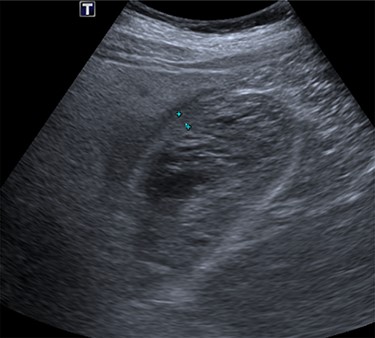

Intravenous broad-spectrum antibiotics were commenced, and the patient was admitted to the surgical ward and fasted for an MRI liver with gadolinium contrast. The MRI revealed no convincing features of malignancy; however, the gallbladder was distended with heterogeneous, predominantly low T1 and T2 content and demonstrating no internal enhancement, as seen in Fig. 2. These findings suggested the presence of sludge and/or luminal blood clod, and a further ultrasound (US) of the gallbladder was recommended. US scan, as shown in Fig. 3, confirmed cholecystitis with no evidence of cholelithiasis.

US scan of the patient, demonstrating a thick-walled gallbladder, with no evidence of calculi.